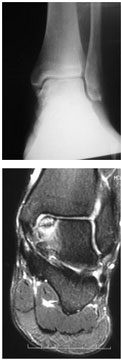

Artroscopia para Lesão Osteocondral do Tálus (LOT)

Usando o probe, avaliamos o amolecimento da cartilagem e a dimensão do defeito. Reduzimos e fixamos as lesões osteocondrais com osso subcondral em boas condições. O desbridamento deve remover a cartilagem solta (corpos livres), porém, a cartilagem intacta, mas amolecida, deve ser mantida. Nas lesões osteocondrais crônicas firmemente aderidas ao tálus, utilizamos perfurações (drilling), em espaços de 3 a 5 mm e profundidade de 10 mm. Nas lesões descoladas, retiramos os fragmentos e fazemos o drilling do leito remanescente.

Em lesões císticas com superfície de cartilagem intacta, indicamos a curetagem da lesão com enxertia e a manutenção da cartilagem intacta. Sendo assim, em lesões císticas que apresentam também lesão da cartilagem sobrejacente, debridamos toda a área e removemos os corpos livres. Depois, fazemos o drilling e avaliamos a necessidade de enxertia com ou sem cola de fibrina. Outra indicação é a realização de microfraturas. Pacientes com lesões císticas maiores que 7-8 mm podem ser candidatos a técnicas de restauração (transplante autólogo de condrócitos).